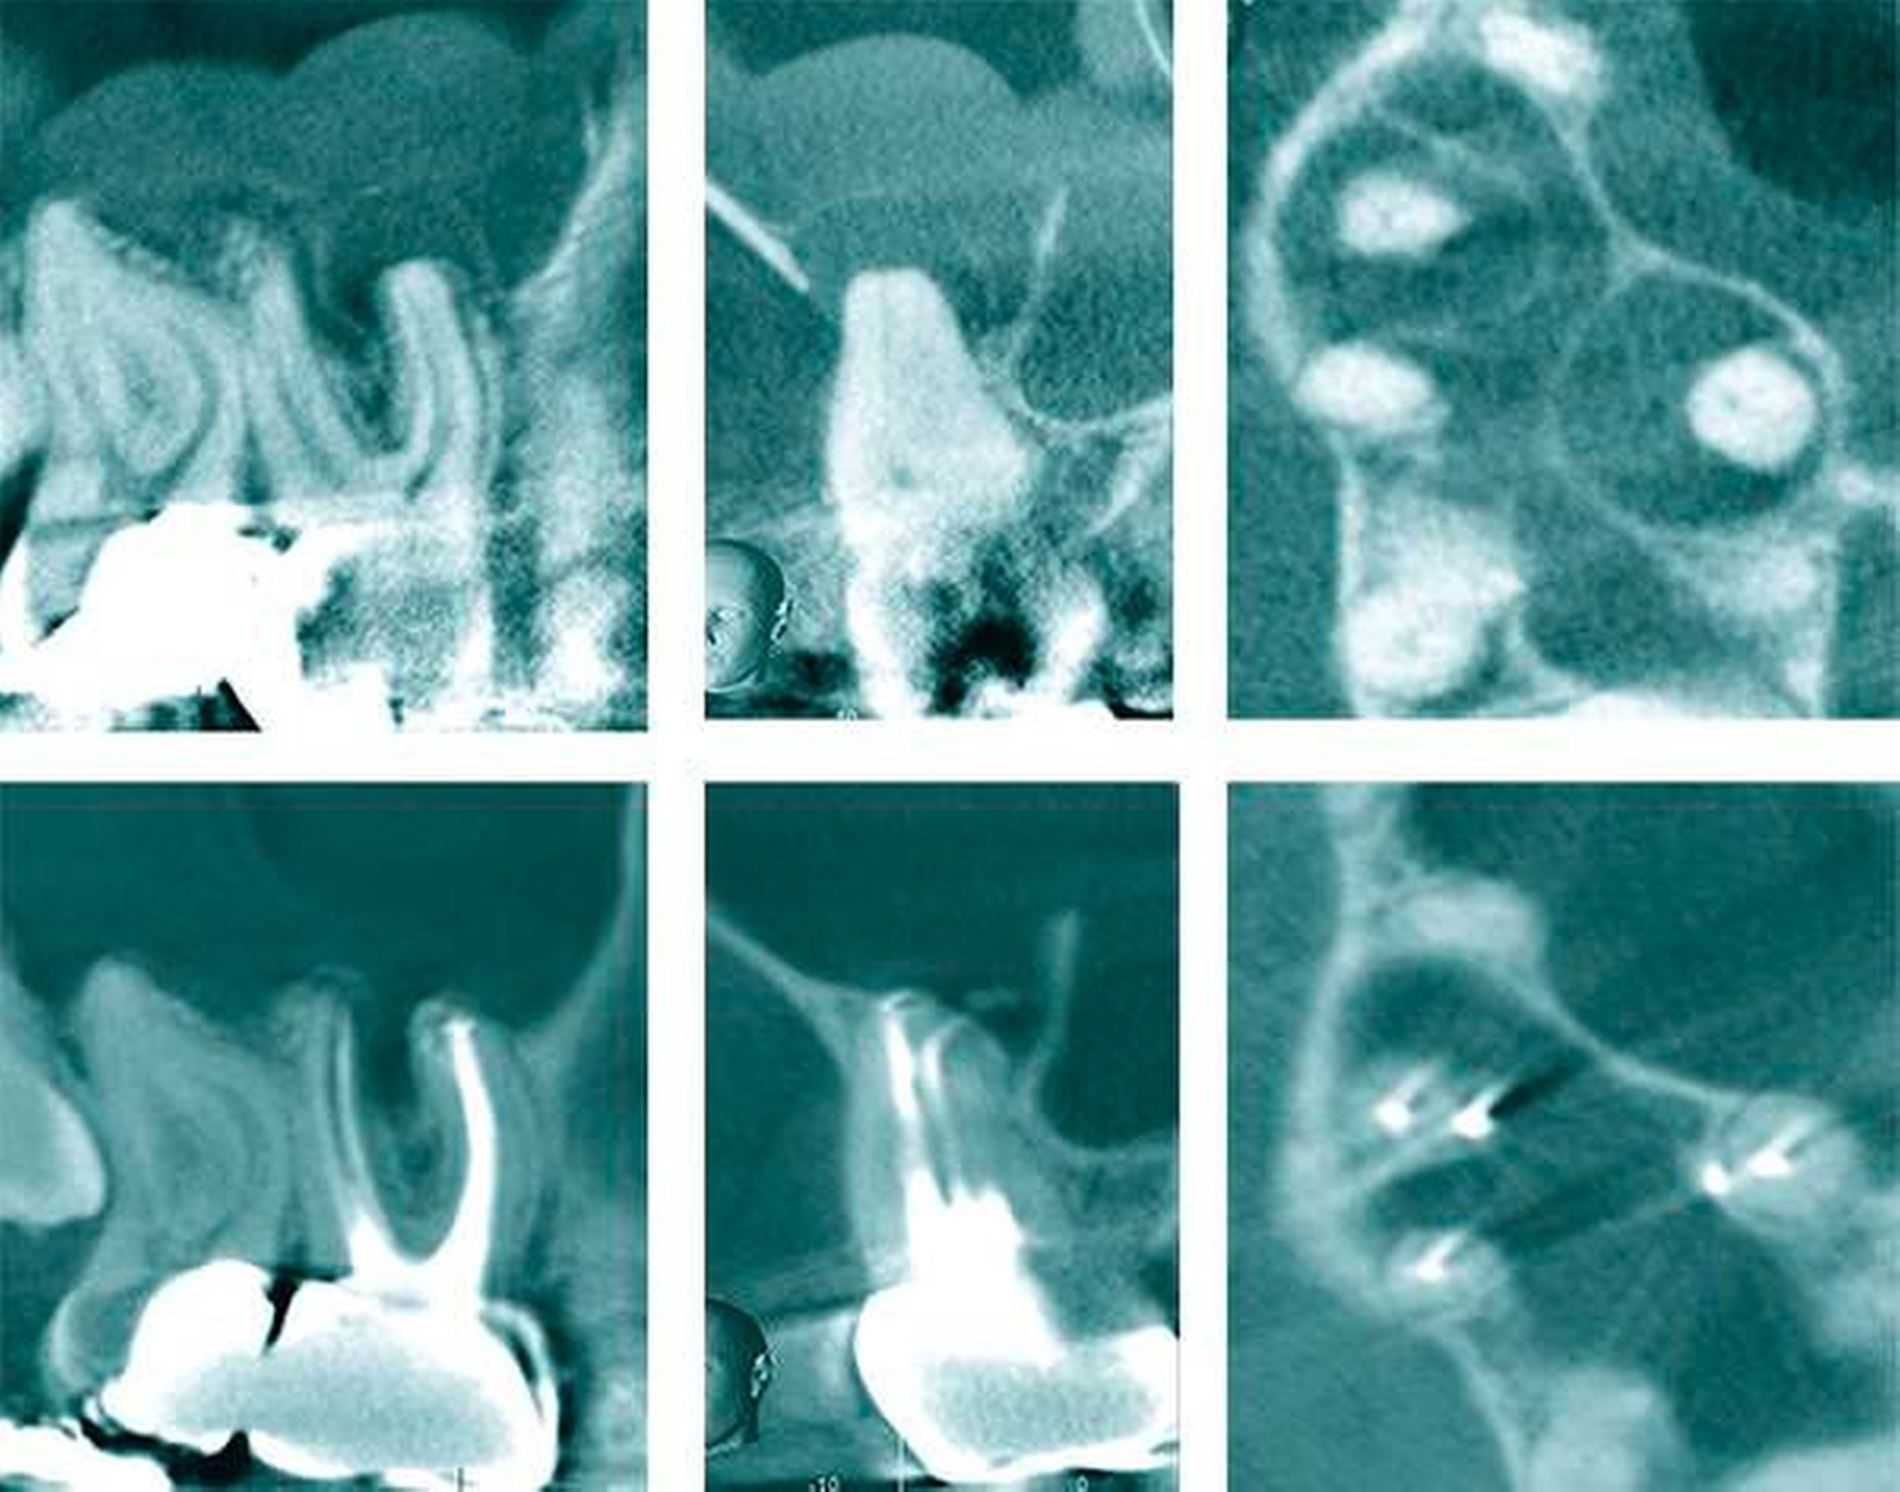

Die aktuelle Forschung kann auf hochauflösende Verfahren zur Ermittlung von Wurzelkanalsystemen zurückgreifen. Die destruktiven Verfahren werden dabei mehr und mehr von nondestruktiven Verfahren (MikroCT, NanoCT, MRT) abgelöst [Parkinson & Sasov, 2008; Paqué et al., 2010] (Abbildungen 2 und 3). Mit der dentalen Digitalen Volumentomografie (DVT) gelingt es erstmals am Patienten, die tatsächliche Form und den Verlauf von Wurzeln in Beziehung zu pathologischen Prozessen darzustellen (Abbildung 4) und aus der Form der Wurzel Rückschlüsse auf die Anzahl und die genaue Lage der Wurzelkanäle zu ziehen [DVT-Leitlinie DGZMK S2, 2009; Patel, 2009; Michetti et al., 2010].

Das Auffinden des MB2 bei oberen zweiten Molaren kann sich erheblich unterscheiden (Abbildung 3). Insbesondere bei bandförmigen Fusionen der mesiobukkalen und der palatinalen Wurzel bestehen mehrere Möglichkeiten des Wurzelkanalzugangs. So kann man auch in seltenen Fällen den zweiten mesiobukkalen Wurzelkanaleingang im koronalen Wurzeldrittel des palatinalen Wurzelkanals auffinden (Abbildungen 17 und 18, Abbildung 3).

Die Auseinandersetzung mit der bisweilen sehr komplexen Anatomie des Wurzelkanalsystems soll den Zahnarzt keineswegs entmutigen – im Gegenteil: Mit mehr Wissen und Erfahrung können auch schwierige Fälle erfolgreicher therapiert werden. Die dreidimensionale Darstellung des Wurzelkanalsystems mithilfe der Computertomografie führt zu einem besseren Verständnis einer komplexen anatomischen Struktur und ermöglicht die Entwicklung neuer minimalinvasiver Behandlungstechniken. Die Indikation zur Anfertigung einer dentalen DVT-Aufnahme ist jeweils individuell zu bestimmen und orientiert sich am Nutzen für den Patienten [Schulze et al., 2013]. Präoperative DVT-Aufnahmen erhöhen die diagnostische Sicherheit und beeinflussen signifikant die Therapieentscheidung [Mota de Almeida et al., 2014]. Das Ermitteln der tatsächlichen Wurzelform und möglicher tiefer Aufzweigungen von Wurzelkanälen kann dann den Erfolg der Therapie positiv beeinflussen, wenn gleichzeitig die Informationen aus der dentalen DVT mit einer optischen Vergrößerung (Lupenbrille 6x oder Dentalmikroskop) am Patienten wieder aufgefunden werden können.